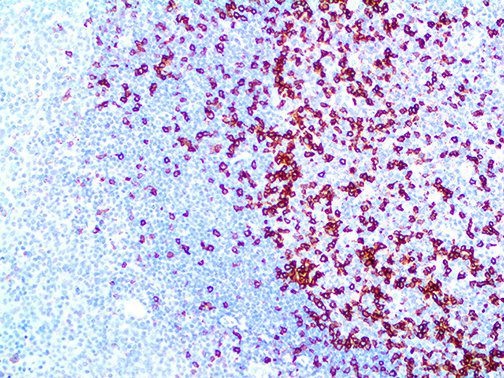

It is the ICU physician who is most likely to witness one of the deadliest manifestations of the abnormal immunological response, the cytokine storm syndrome (CSS). This response is also referred to by some as the cytokine release syndrome (CRS). CSS is characterized by continuous activation and expansion of macrophage and lymphocyte populations, which secrete large amounts of cytokines, causing the cytokine storm. This massive cytokine release is akin to hemophagocytic lymphohistiocytosis (HLH) disease, a syndrome characterized by initial unchecked and persistent activation of cytotoxic T lymphocytes and NK cells.

Clinical and laboratory manifestations of HLH include fever, enlarged liver and/or spleen, neurologic dysfunction, coagulopathy, liver dysfunction, cytopenias (i.e., low levels of erythrocytes, leukocytes, and/or platelets), hypertriglyceridemia, hyperferritinemia, hemophagocytosis, and eventually diminished NK cell activity as the immune system becomes progressively paralyzed. HLH can be familial (primary HLH) or secondary to another disease process (sHLH), such as rheumatic disease, in which it is referred to as macrophage activation syndrome (MAS, characterized by elevated ferritin).